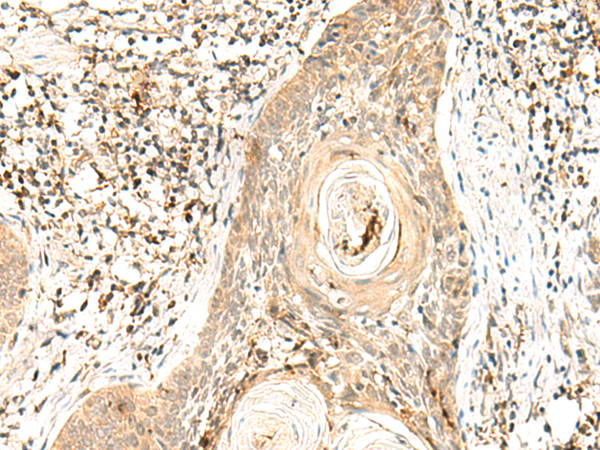

IHC positive control: |

Human esophagus cancer and Human tonsil |